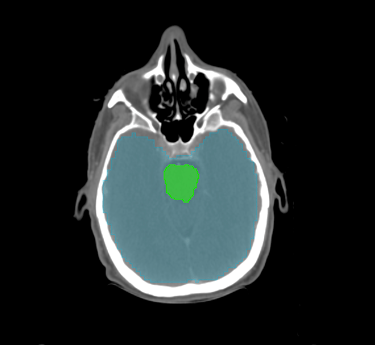

Head & Neck

Choose from a combined structure volume including BrainStem, Brain, Chaism, Mandible, Optic nerves Trachea and many more, or choose individual split sub-levels.